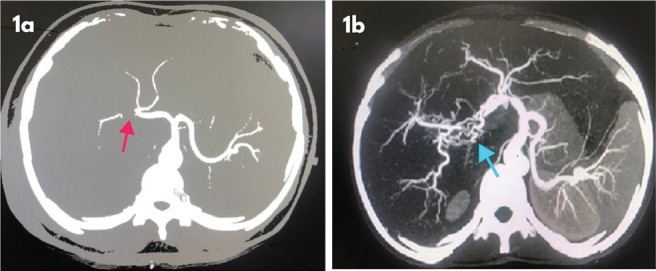

Material and methods: This prospective study was done between November 2019 and December 2022. Patients presenting with post-cholecystectomy bile duct injury were investigated to detect vascular injury using computed tomography angiography. A comparative analysis of clinical presentation, and results of biliary reconstruction was performed on patients with and without concomitant vascular injury. McDonald criteria were used to grade the outcome of biliary reconstruction in these patients.

Results: We studied 48 patients with bile duct injury of which 19 (39%) patients had concomitant vascular injury on imaging. Concomitant vascular injury was found in 87% and 42% of patients with Strasberg type 4 and type 3 injury, respectively. At presentation, the incidence of liver abscesses was significantly higher in patients with concomitant vascular injury. After two years of biliary repair, 75% of patients had McDonald Grade A status, irrespective of whether vascular injury was present.